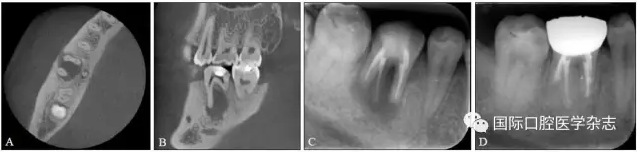

典型病例2 46牙頰側(cè)竇道經(jīng)久未愈,行根尖外科手術(shù)后竇道愈合(圖2)。

A、B:術(shù)前CBCT圖像;C:術(shù)前X線充填片;D:術(shù)后1年復(fù)查X線片,病變愈合。

圖 2 46牙根尖周炎經(jīng)顯微根尖外科手術(shù)后愈合